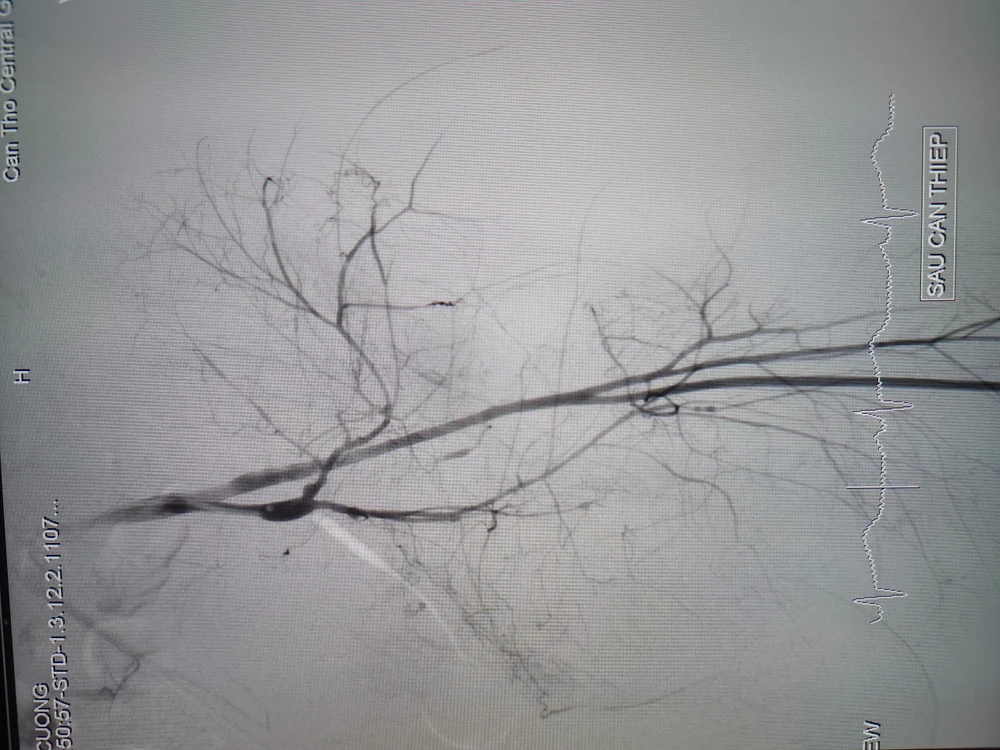

Hình ảnh trước và sau can thiệp nội mạch cho bệnh nhân bị tường đè nguy kịch. Ảnh: BVCC

Sau đó, các bác sĩ can thiệp mạch chụp mạch số hóa xóa nền mạch máu vùng chậu phát hiện ổ thoát mạch từ nhánh động mạch chậu trong (T), tiến hành nút mạch cầm máu ổ thoát mạch lưu lượng lớn với thời gian 10 phút.

Sau can thiệp nút mạch, tình trạng huyết động bệnh nhân cải thiện tốt mạch rõ. Huyết áp ổn định và được chuyển hậu phẫu, điều chỉnh rối loạn đông máu và tiếp tục thực hiện các can thiệp tiếp theo.